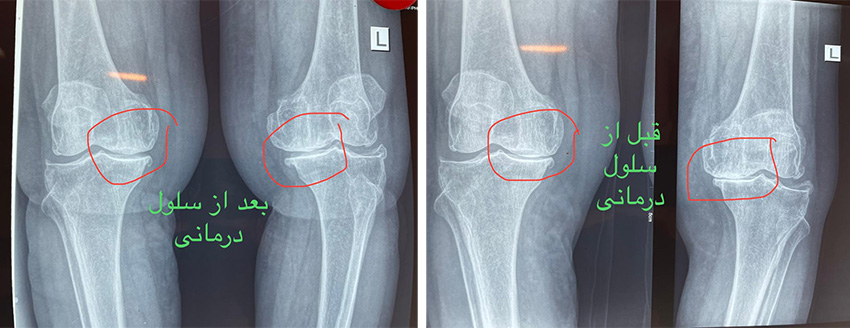

سلول درمانی زانو قبل و بعد

چندین مطالعه و کارآزمایی بالینی نشان داده اند که تزریق داخل مفصلی سلول های بنیادی مزانشیمال می تواند در بهبود عملکرد و کاهش درد در بیماران مبتلا به آرتروز زانو موثر باشد. برخی نتایج شامل بهبود نمرات درد، افزایش محدوده حرکتی مفصل و بازسازی قسمتی از غضروف آسیب دیده بوده است.